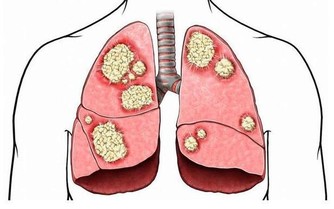

2、下肢動脈閉塞患者

下肢動脈閉塞的表現雖然是下肢缺血,但是熱水泡腳並不能擴張閉塞的血管。當然,通暢動脈的擴張,只是增加了正常組織的血流,而缺血組織可能因為“盜血”現象,更加缺血。相關數據說明,周圍溫度的升高,能夠添加安排的耗氧量,加重缺血。